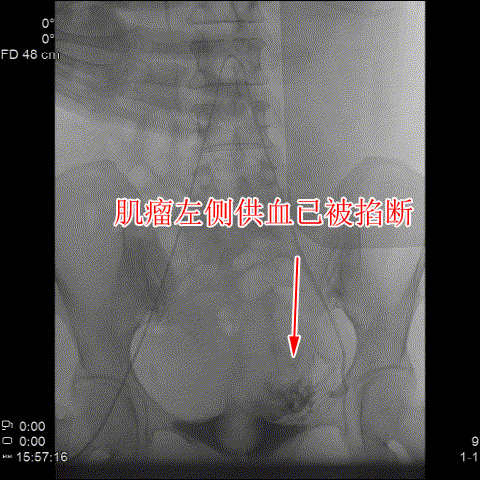

△術後造影可見肌瘤左右側的供血已被掐斷。